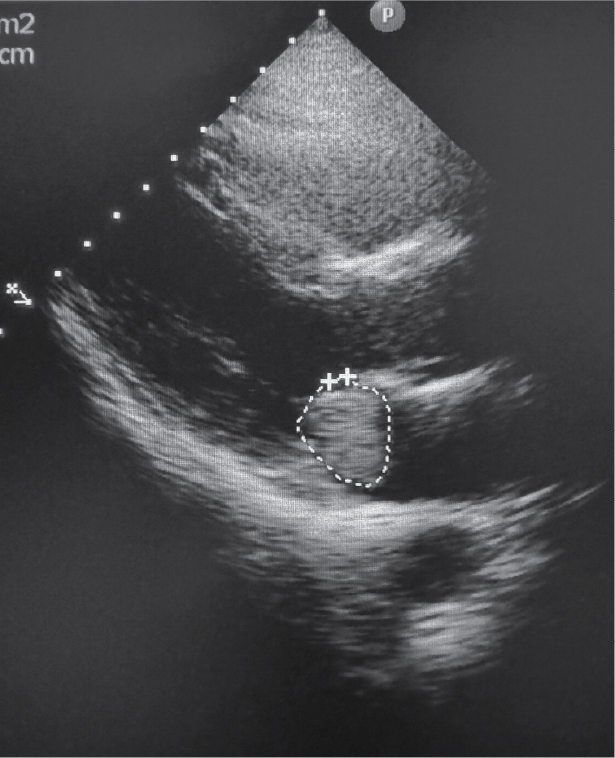

Chest X-ray, electrocardiography, and abdominal ultrasound were normal. Echocardiography revealed a pedunculated left atrial mass measuring 2.53 × 1.76 cm suggestive of myxoma (Fig. 1). TEE confirmed this finding. Coronary angiography showed normal

Figure 1. Echocardiography showing a mass of 2.53 × 1.76 cm in the left atrium close to the mitral valve orifice.

Symptoms of myxomas vary depending on their effects, whether obstructive, embolic, or through biochemical mechanisms. Our patient did not exhibit systemic symptoms or elevated inflammatory markers suggestive of vasoactive substance secretion by the tumor.

There were no syncopal episodes or signs of flash pulmonary edema indicative of significant valvular obstruction, nor symptoms suggestive of systemic or pulmonary embolism. The tumor measured 2.53 × 1.76 cm, with larger tumors (>5 cm) more likely

Echocardiography, performed as part of cardiac screening for symptoms, unexpectedly detected a left atrial mass. It remains the preferred diagnostic modality, with TEE offering higher sensitivity. Cardiac MRI can provide additional details on tumor